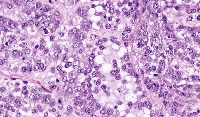

This is an AI laboratory project by Linette Dannah Cartagena, a second year medical student. Ovarian cancer can be classified into four main types: epithelial tumors, germ cell tumors, stromal tumors, and small cell carcinoma of the ovary. This model aims to recognize each type through AI. All one has to do is to simply by upload a photo of the histological slide.